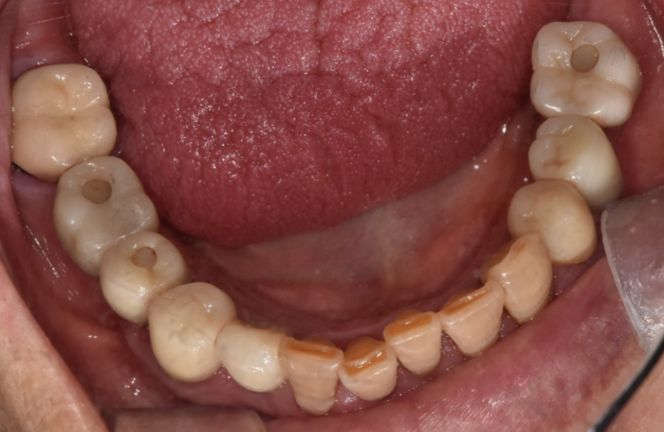

<완성 사진>

240118

여기저기 충치도 있고

뿌리만 남아있었는데 싹~ 치료하신 모습을 보니

뿌듯합니다.

깔끔해졌습니다.